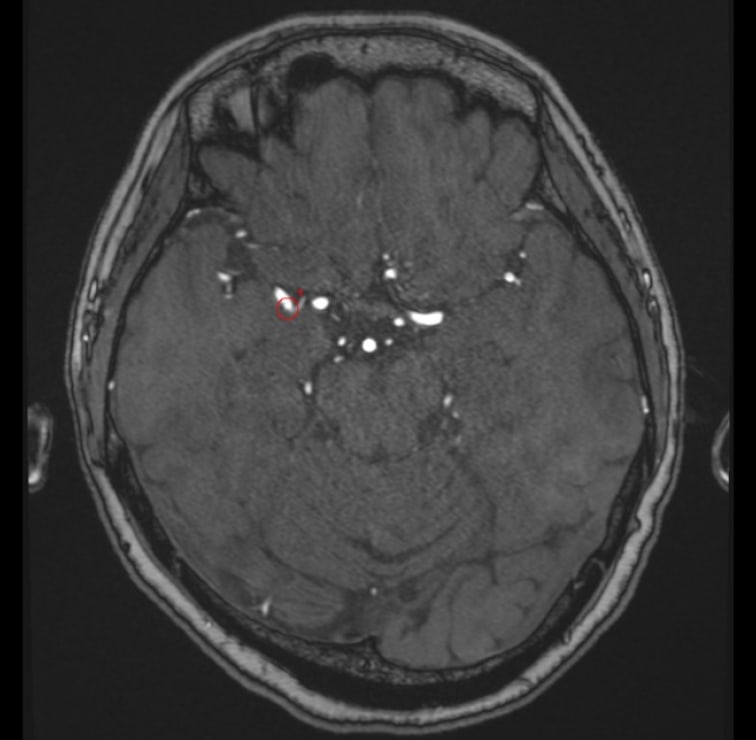

解析事例

中大脳動脈